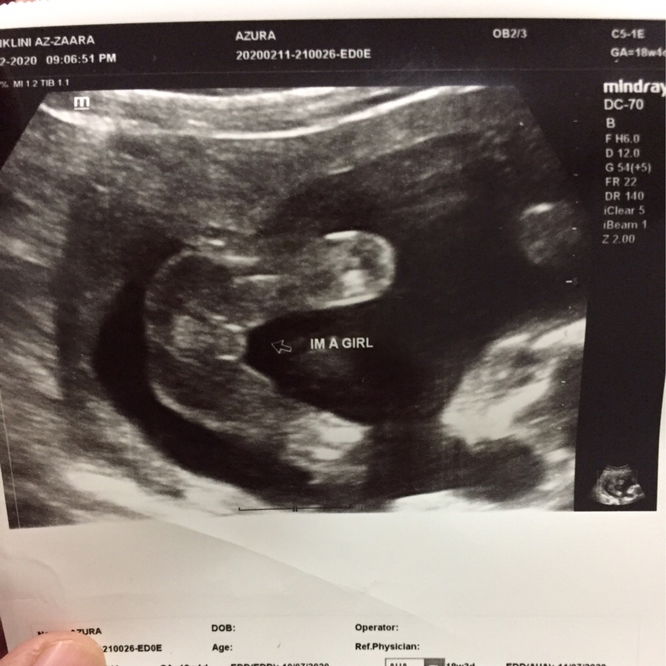

Scan 18week

Balik dari keje tadi perut sye sakit sgt, risau jgk ada apa apa dengan kandungan sye, jadi sye buat keputusan untuk pegi Scan kandungan sye, Alhamdulillah baby takde pape, ? doctor ckp sye ade gastrik dan angin tuh yg sakit perut, dlm pada masa yg sama kandungan sye 18minggu doc daa boleh nampak jantina 80% Perempuan ? awal sangat dah nampak ? doctor tuh baik sgt, peramah baby sye active dlm kandungan siap posing kaki kat atas tangan kat kepala ? tgh bersantai tapi yang peliknya, ramai ckp 6bulan daa boleh scan jantina ke ada yg boleh scan nampak jantina awal?

Alhamdulillah syukur tahniah sis. Saya pun scan dekat klinik yg sma. 16weeks doc dah nampak 80% "burger sign" and 27weeks buat details scan confirm girl. ☺

Klu bby bg kerjasama masa scan 17w pun dah npk... Tp bukan semua bby nak bg tgk tu. Mcm sya 20w pun x bg tgk.. 23w3d br bby bg tgk

Alhamdulillah..sama la kita bby girl jgk,sy scan dlu msa 5bulan dh npk jantina nye..Dr kata burger belah elok ja hehe

tulaa org ckp kalau boleh scan time 6bulan baru nampak, time tuh cuma risau je, perut sakit tuh pegi scan, sekali dia angkat kaki sampai ke dada 😅

18 weeks bleh dah nmpak kalau babynk tnjuk. Sy hritu baby dok kepit2 lg.. tahniahhh geng mami 🥰